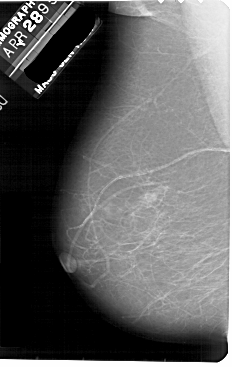

A_1881_1.RIGHT_MLO

RIGHT_MLO LINES 5491 PIXELS_PER_LINE 3256 BITS_PER_PIXEL 12 RESOLUTION 43.5 OVERLAY

FILE: A_1881_1.RIGHT_MLO.OVERLAY

TOTAL_ABNORMALITIES 1

ABNORMALITY 1

LESION_TYPE MASS SHAPE LOBULATED MARGINS ILL_DEFINED

ASSESSMENT 4

SUBTLETY 4

PATHOLOGY BENIGN

TOTAL_OUTLINES 1

BOUNDARY